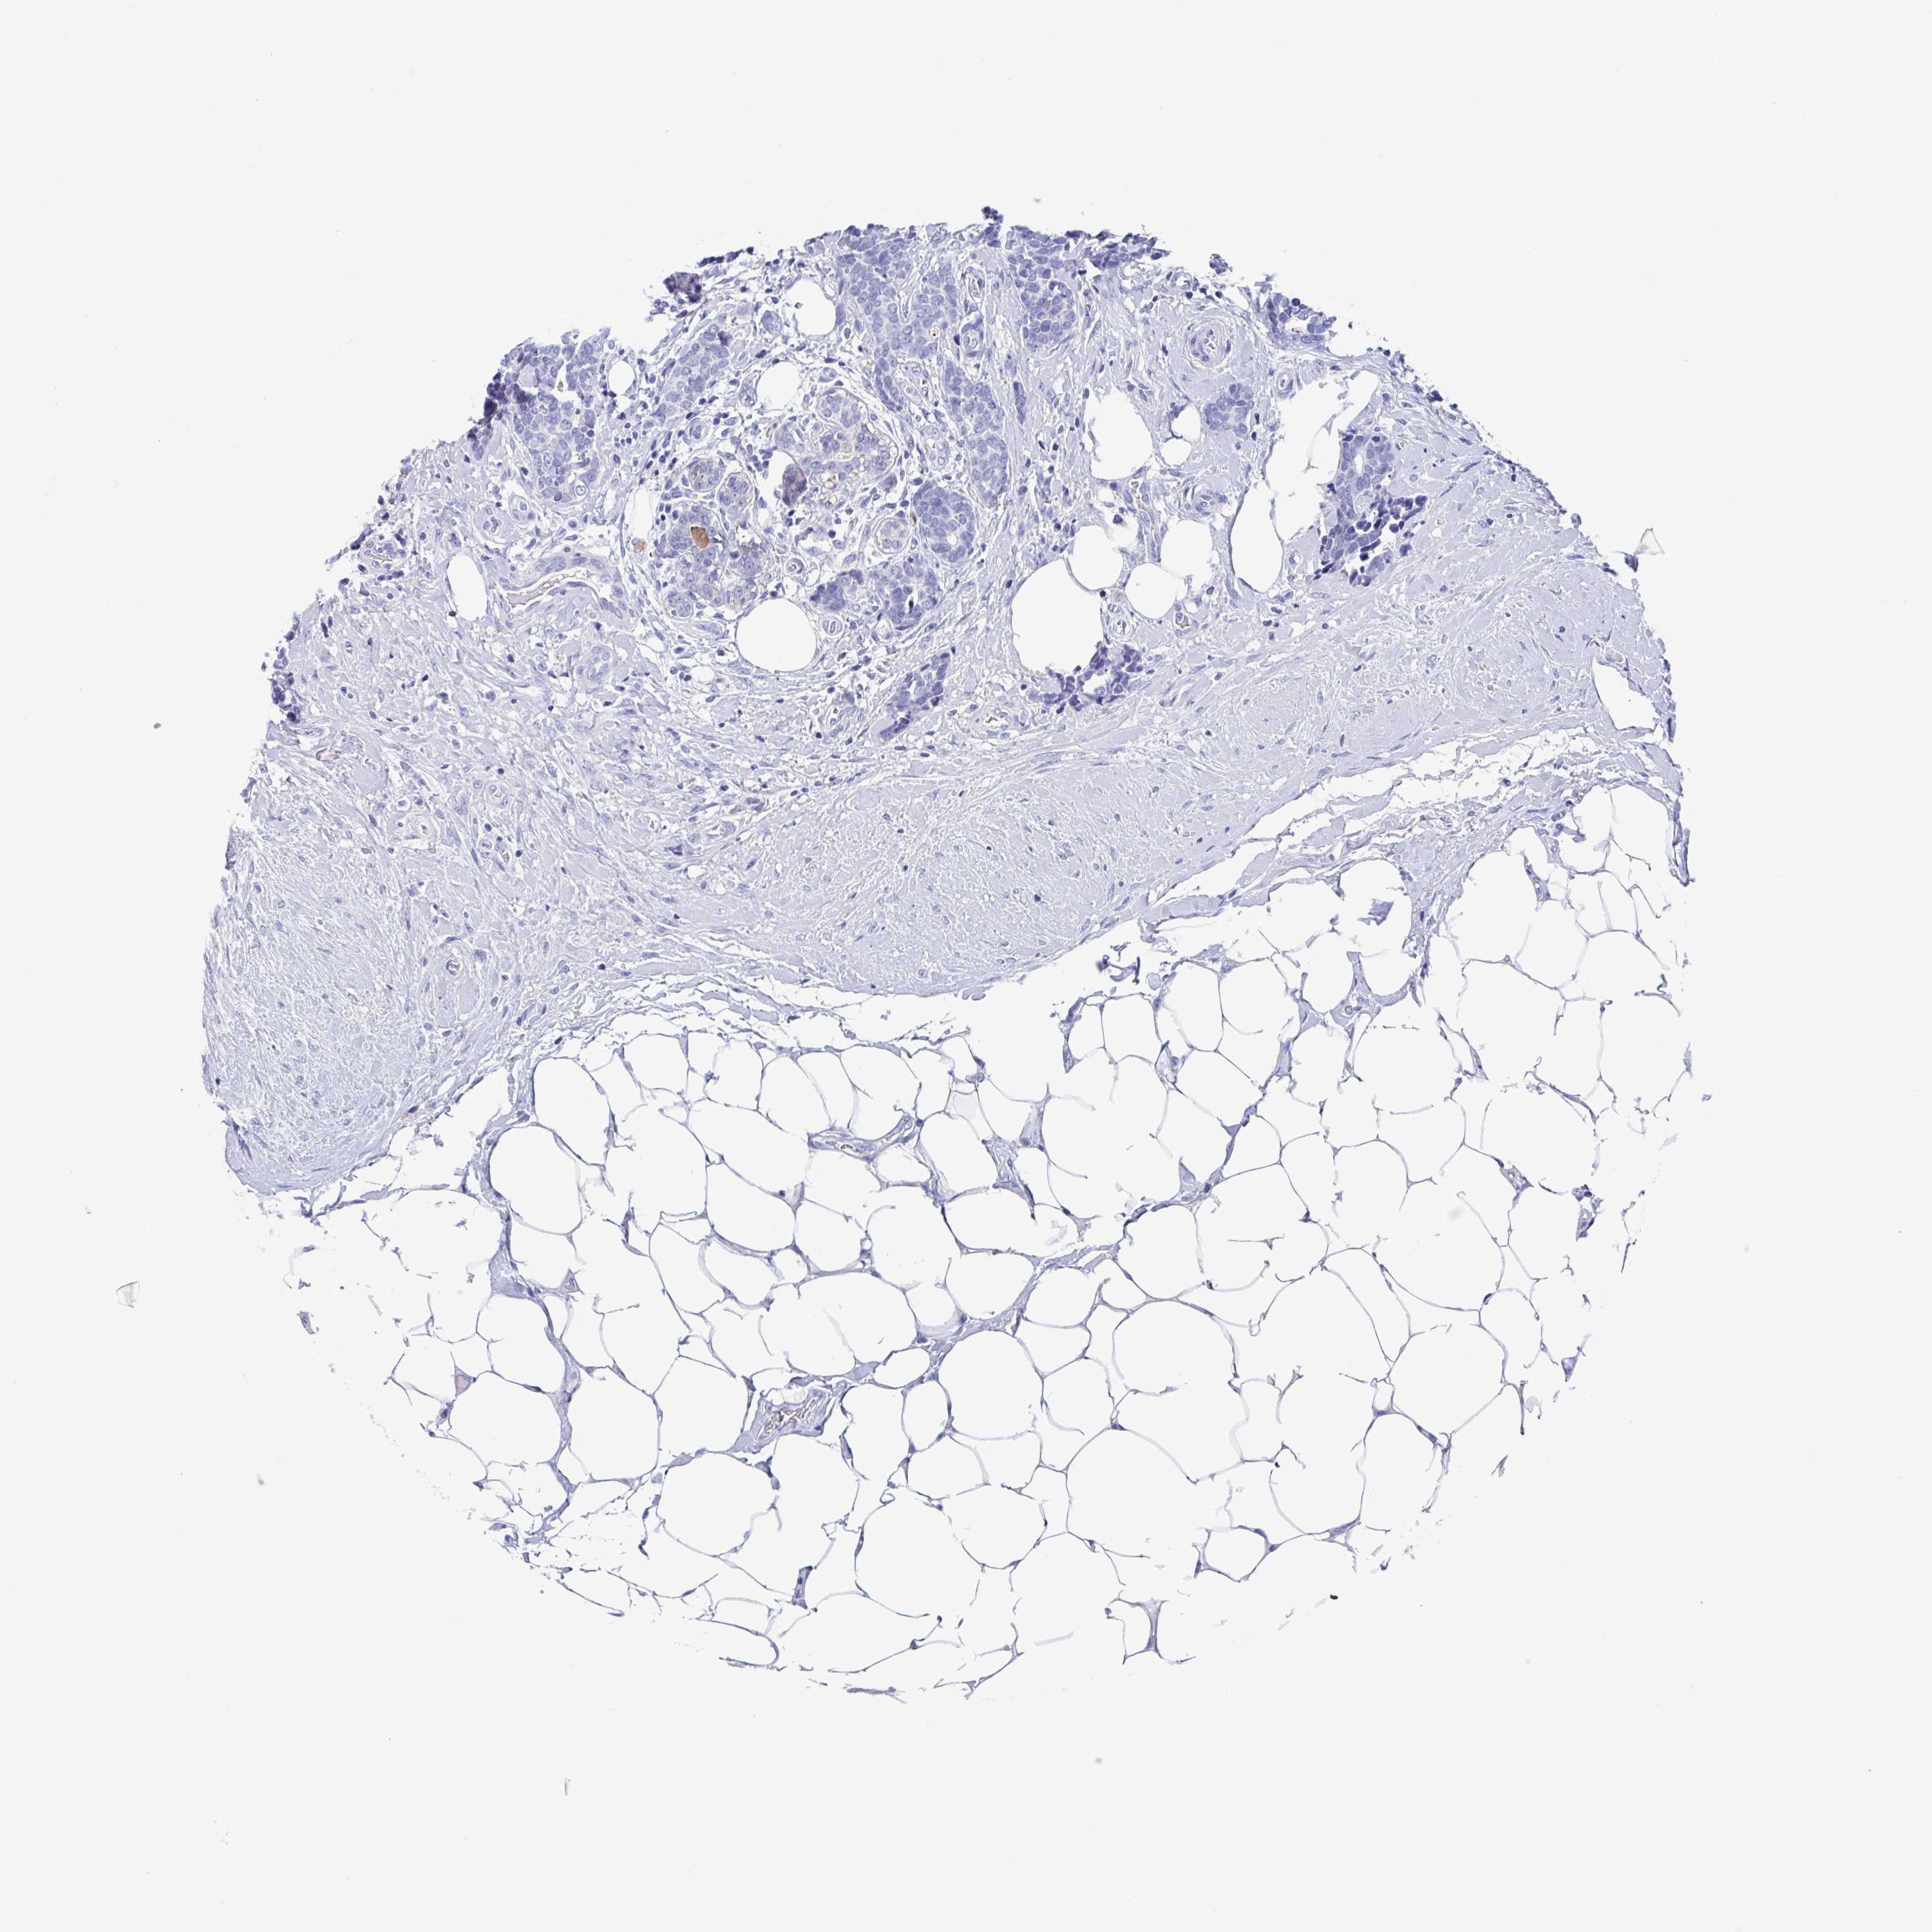

BRCA TCGA BRCA VALIDATION PROTEIN EXPRESSION

ANTIBODIES

AND

VALIDATION